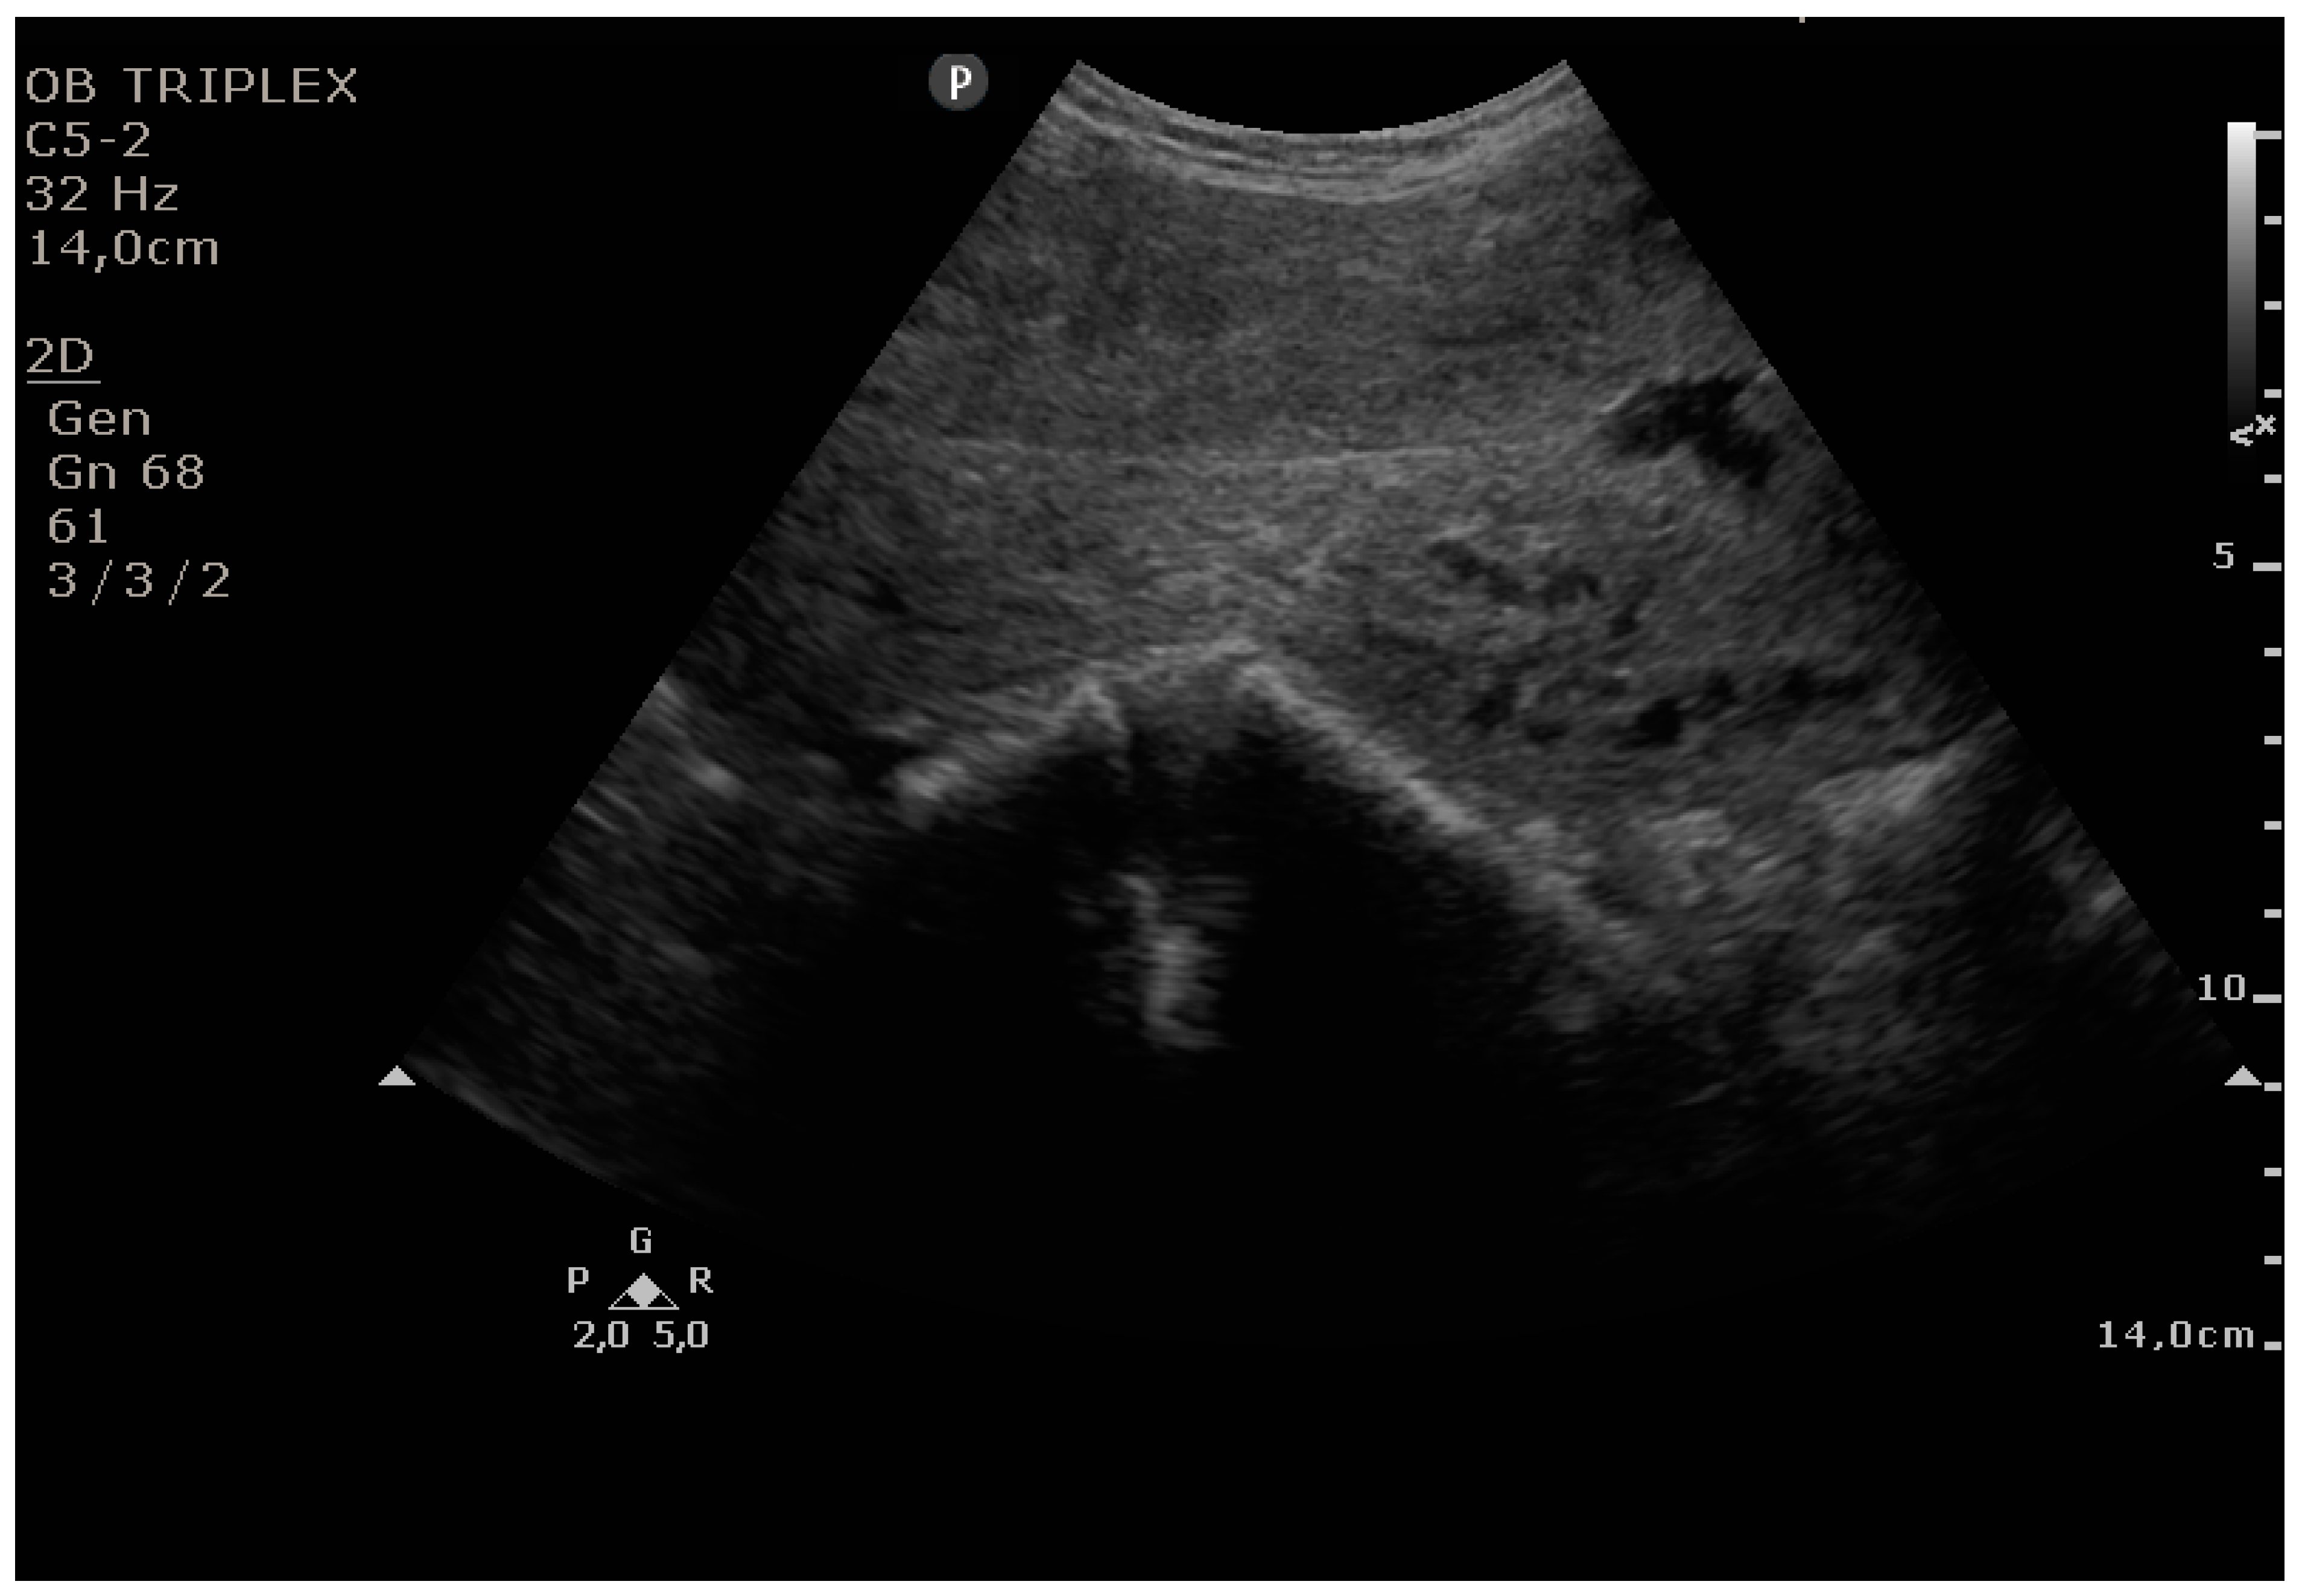

The PUUS method evaluates the proportion of the endometrial length occupied by blood or debris, as follows (Figure 1, Figure 2, Figure 3, Figure 4 and Figure 5):

Grade 3: less than three-quarters of the endometrial length occupied by blood or debris;

Figure 4. Grade 3: less than three-quarters of the endometrial length occupied by blood or debris.